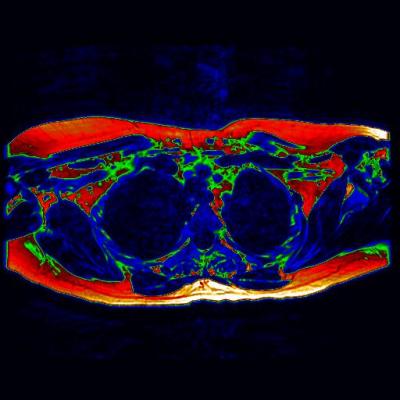

The first MRI scan to show 'brown fat' in a living adult could prove to be an essential step towards a new wave of therapies to aid the fight against diabetes and obesity.

Researchers from Warwick Medical School and University Hospitals Coventry and Warwickshire NHS Trust used a magnetic resonance imaging (MRI) based method to identify and confirm the presence of brown adipose tissue in a living adult.

Unlike the PET data which only displays activity, the MRI can show brown fat content whether active or not – providing a detailed insight into where it can be found in the adult body. This information could prove vital in the creation of future therapies that seek to activate deposits of brown fat.

Dr Barber added, "The MRI allows us to distinguish between the brown fat, and the more well-known white fat that people associate with weight gain, due to the different water to fat ratio of the two tissue types. We can use the scans to highlight what we term 'regions of interest' that can help us to build a picture of where the brown fat is located."